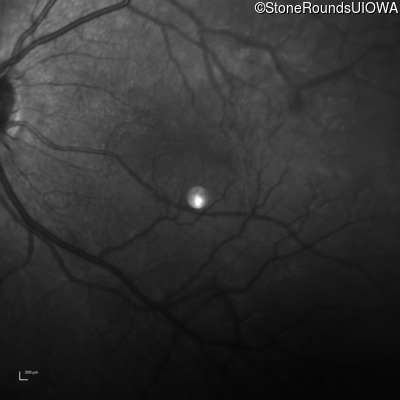

This 9 year old male was noted to have some crossing of his eyes at 2 months of age and the eye exam which followed identified a retinal lesion in the right eye. When he was six years old an epiretinal membrane was noted in his left eye. Two years later it was decided that it was a thin hamartoma in that eye as well. He underwent neuroimaging at age 7 which identified bilateral acoustic neuromas.